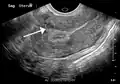

A very large (9 cm) fibroid of the uterus which is causing pelvic congestion syndrome as seen on ultrasound

-